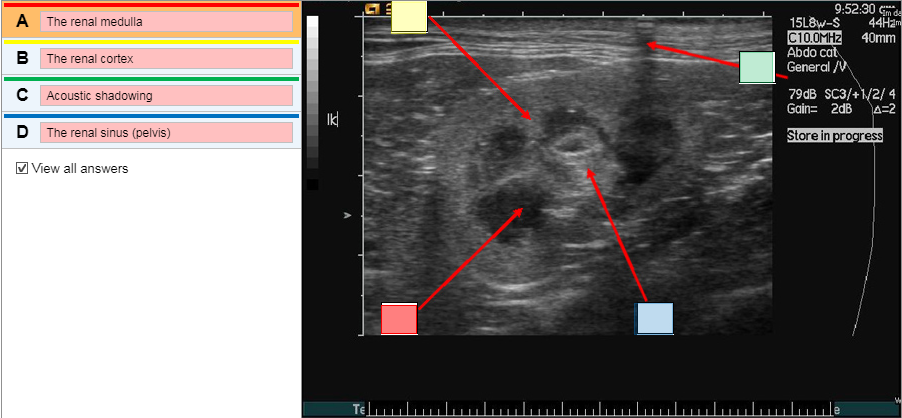

On the following transverse image of both kidneys of a cat, which appear normal, identify the following structures by selecting the appropriate label and placing it in to the correct text box.